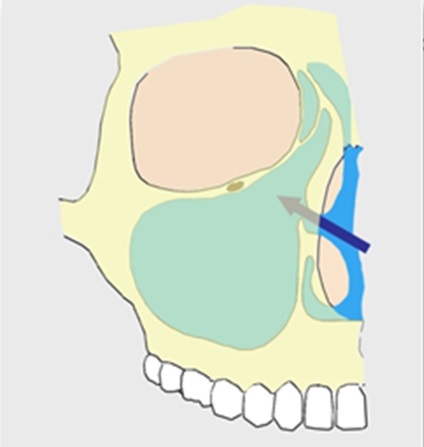

Ciszta csak sebészileg el kell távolítani, igénylő endoszkópos vagy a hagyományos radikális műtétre az arcüreg. Az endoszkópos műtét kétségtelenül előnyös, mert kíséri minimális sebészi trauma, de bizonyos esetekben még mindig szükség van a radikális műtét.

Ebben az esetben a szigetelés és eltávolítása ciszta héja nem fog nélkül hozzáférést az oldalán a száját. Az ilyen műveletek, ellentétben az endoszkópos agresszívebb nehezebb tolerálják a betegek, és a legfontosabb, mindig megtartja a sinus hiba elülső fala, úgyhogy minden más esetben, előnyben kell részesíteni pontosan endoszkópos beavatkozást. Endoszkópos eltávolítása ciszták hajtjuk az orron keresztül, és csak azt követeli bővítése természetes anasztomózis közötti sinus és az orrüreg.

Néha elérheti az orron keresztül egészíti ki egy defekt anterior sinus fal, hogy megkönnyítse a munkáját az alsó és a legmélyebb részei az orrmelléküregek, de a szúrás olyan kicsi, hogy, mint általában, a betegek nem veszik észre a lábnyom a szájban.